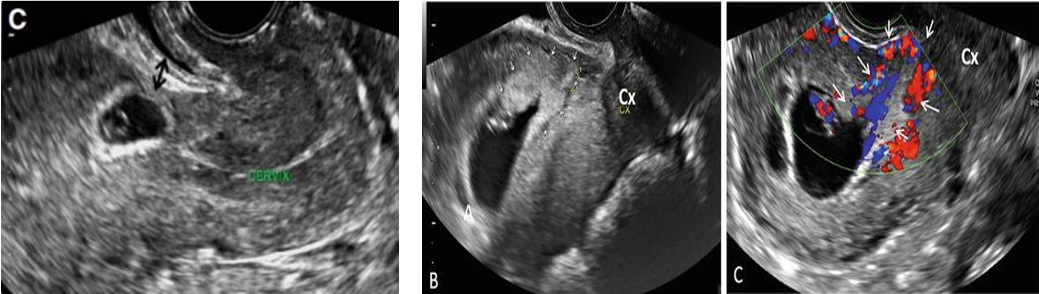

6. CHẨN ĐOÁN

Trên lâm sàng chẩn đoán TNTCSMLT sớm rất khó. Chẩn đoán căn cứ trên tiền sử, bệnh cảnh lâm sàng như đau bụng, rong huyết và quan trọng nhất là siêu âm Doppler màu, một số trường hợp khó cần xác định bằng MRI và nội soi buồng tử cung cũng được dùng trong chẩn đoán.

Siêu âm đầu dò âm đạo có độ nhạy 85%. Siêu âm đầu dò âm đạo giúp quan sát rõ túi thai và tương quan với sẹo MLT. Kết hợp siêu âm qua thành bụng tạo ra hình ảnh rộng của tử cung và phần phụ và đo được khoảng cách giữa túi thai và bàng quang. Qua đó cũng đó được độ dày vách cơ tử cung giữa bàng quang và túi thai.

Tiêu chuẩn chẩn đoán TNTCSMLT trên siêu âm đầu dò âm đạo theo RCOG

• Buồng tử cung trống không có túi thai trong khoang nội mạc tử cung

• Túi thai hoặc khối tế bào nuôi bám vào vùng vết mổ cũ trước ở đoạn eo tử cung

• Lớp cơ tử cung giữa bàng bang và túi thai biến mất hoặc rất mỏng

• Tăng sinh mạch quanh khối qua siêu âm Doppler

• Kênh cổ tử cung trống.

Hình ảnh siêu âm đầu dó âm đạo thai ngoài tử cung ở vết mổ cũ